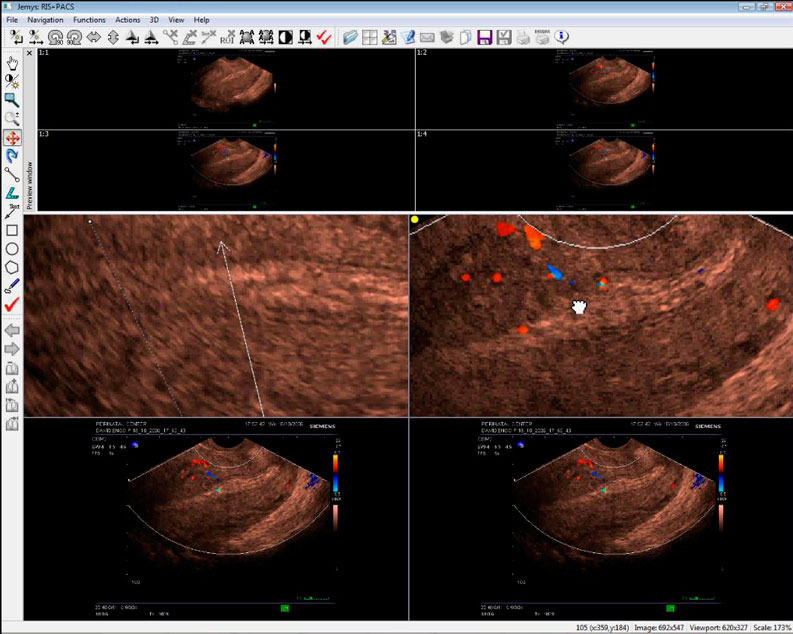

- Обеспечивает представление, обработку и анализ визуальной информации поступающей с различных типов диагностического оборудования с функцией архивирования;

- Выбор строения экрана, создание любой схемы для обзорных и диагностических областей.

- Перегруппировка изображений при помощи мыши, позволяет перетаскивать изображения из области обзорных изображений в область диагностических с использованием метода Drag and Drop.

- Сравнение 2-х исследований: Загрузка двух и более исследований в поле обработки изображений.

- Выделение зон интереса (ROI) и измерение площадей. Возможно выделение прямоугольной, овальной, многоугольной и произвольной зон интереса с указанием средней плотности и площади выделенной области.

- Интерактивное увеличение/уменьшение изображений, режим смещения увеличенного изображения.